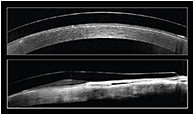

Figure 3. Optical coherence tomography on-eye imaging of the Duette lens.

We refitted the patient with a SynergEyes Duette lens (Figures 2 and 3); these have an 8.4mm spherical GP center with a Dk of 130 and a silicone hydrogel peripheral skirt with a Dk of 84. Parameters of 7.5mm base curve, 14.5mm diameter, and –3.75D power provided a stable visual acuity of 20/30. Her comfort with the lens was excellent; within five days, she was wearing the lens from morning to evening with no objective or subjective signs or symptoms of corneal edema.